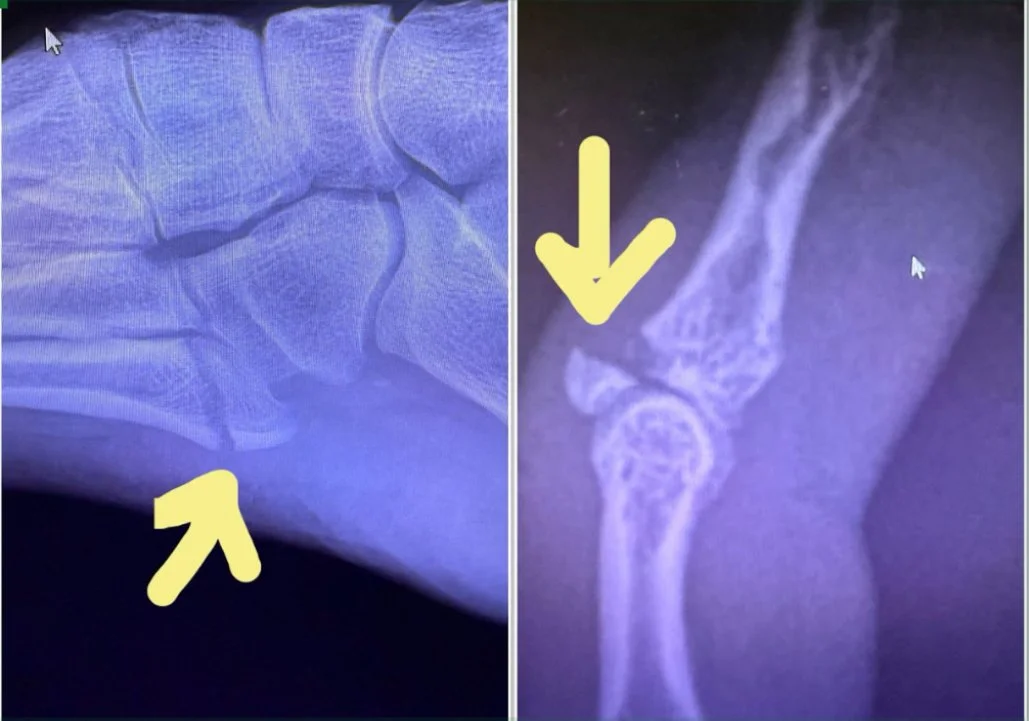

Sitting in my two week follow up appointment yesterday looking at my X-rays with the doctor I asked, “can you tell from looking at these X-rays if I have strong bones?”  He said, “with an X-ray, it’s hard to tell.  If your bones have deteriorated greater than 50%, we would be able to see that on an X-ray.  A DEXA scan is a more accurate reading of bone density.  Based on these images, I am able to see that you do not have osteoporosis beyond 50% bone loss, but beyond that I cannot tell you.”

It’s been a month since I started this blog post and a lot has happened between there and here.  My pinky finger still seems to be completely broken.  When I take the brace off to put fresh tape on, the tip of the finger goes limp so I don’t think the bone ever started the healing process.